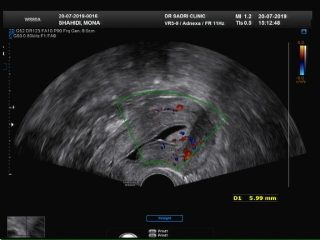

در این مورد ممکن است سونوگرافی کالر داپلر به صورت تکمیلی انجام شود. در تصویر زیر نمونه ای از پولیپ را مشاهده می کنید که توسط کالر داپلر عروق مرکزی تغذیه کننده نشان داده شده است:

عکس مربوط به سونو هیسترو است و در قسمت بالای کاویته رحمی تصویر یک پولیپ با پدیکل عروقی آن که از لایه قدامی اندومتر منشا گرفته رویت میشود: